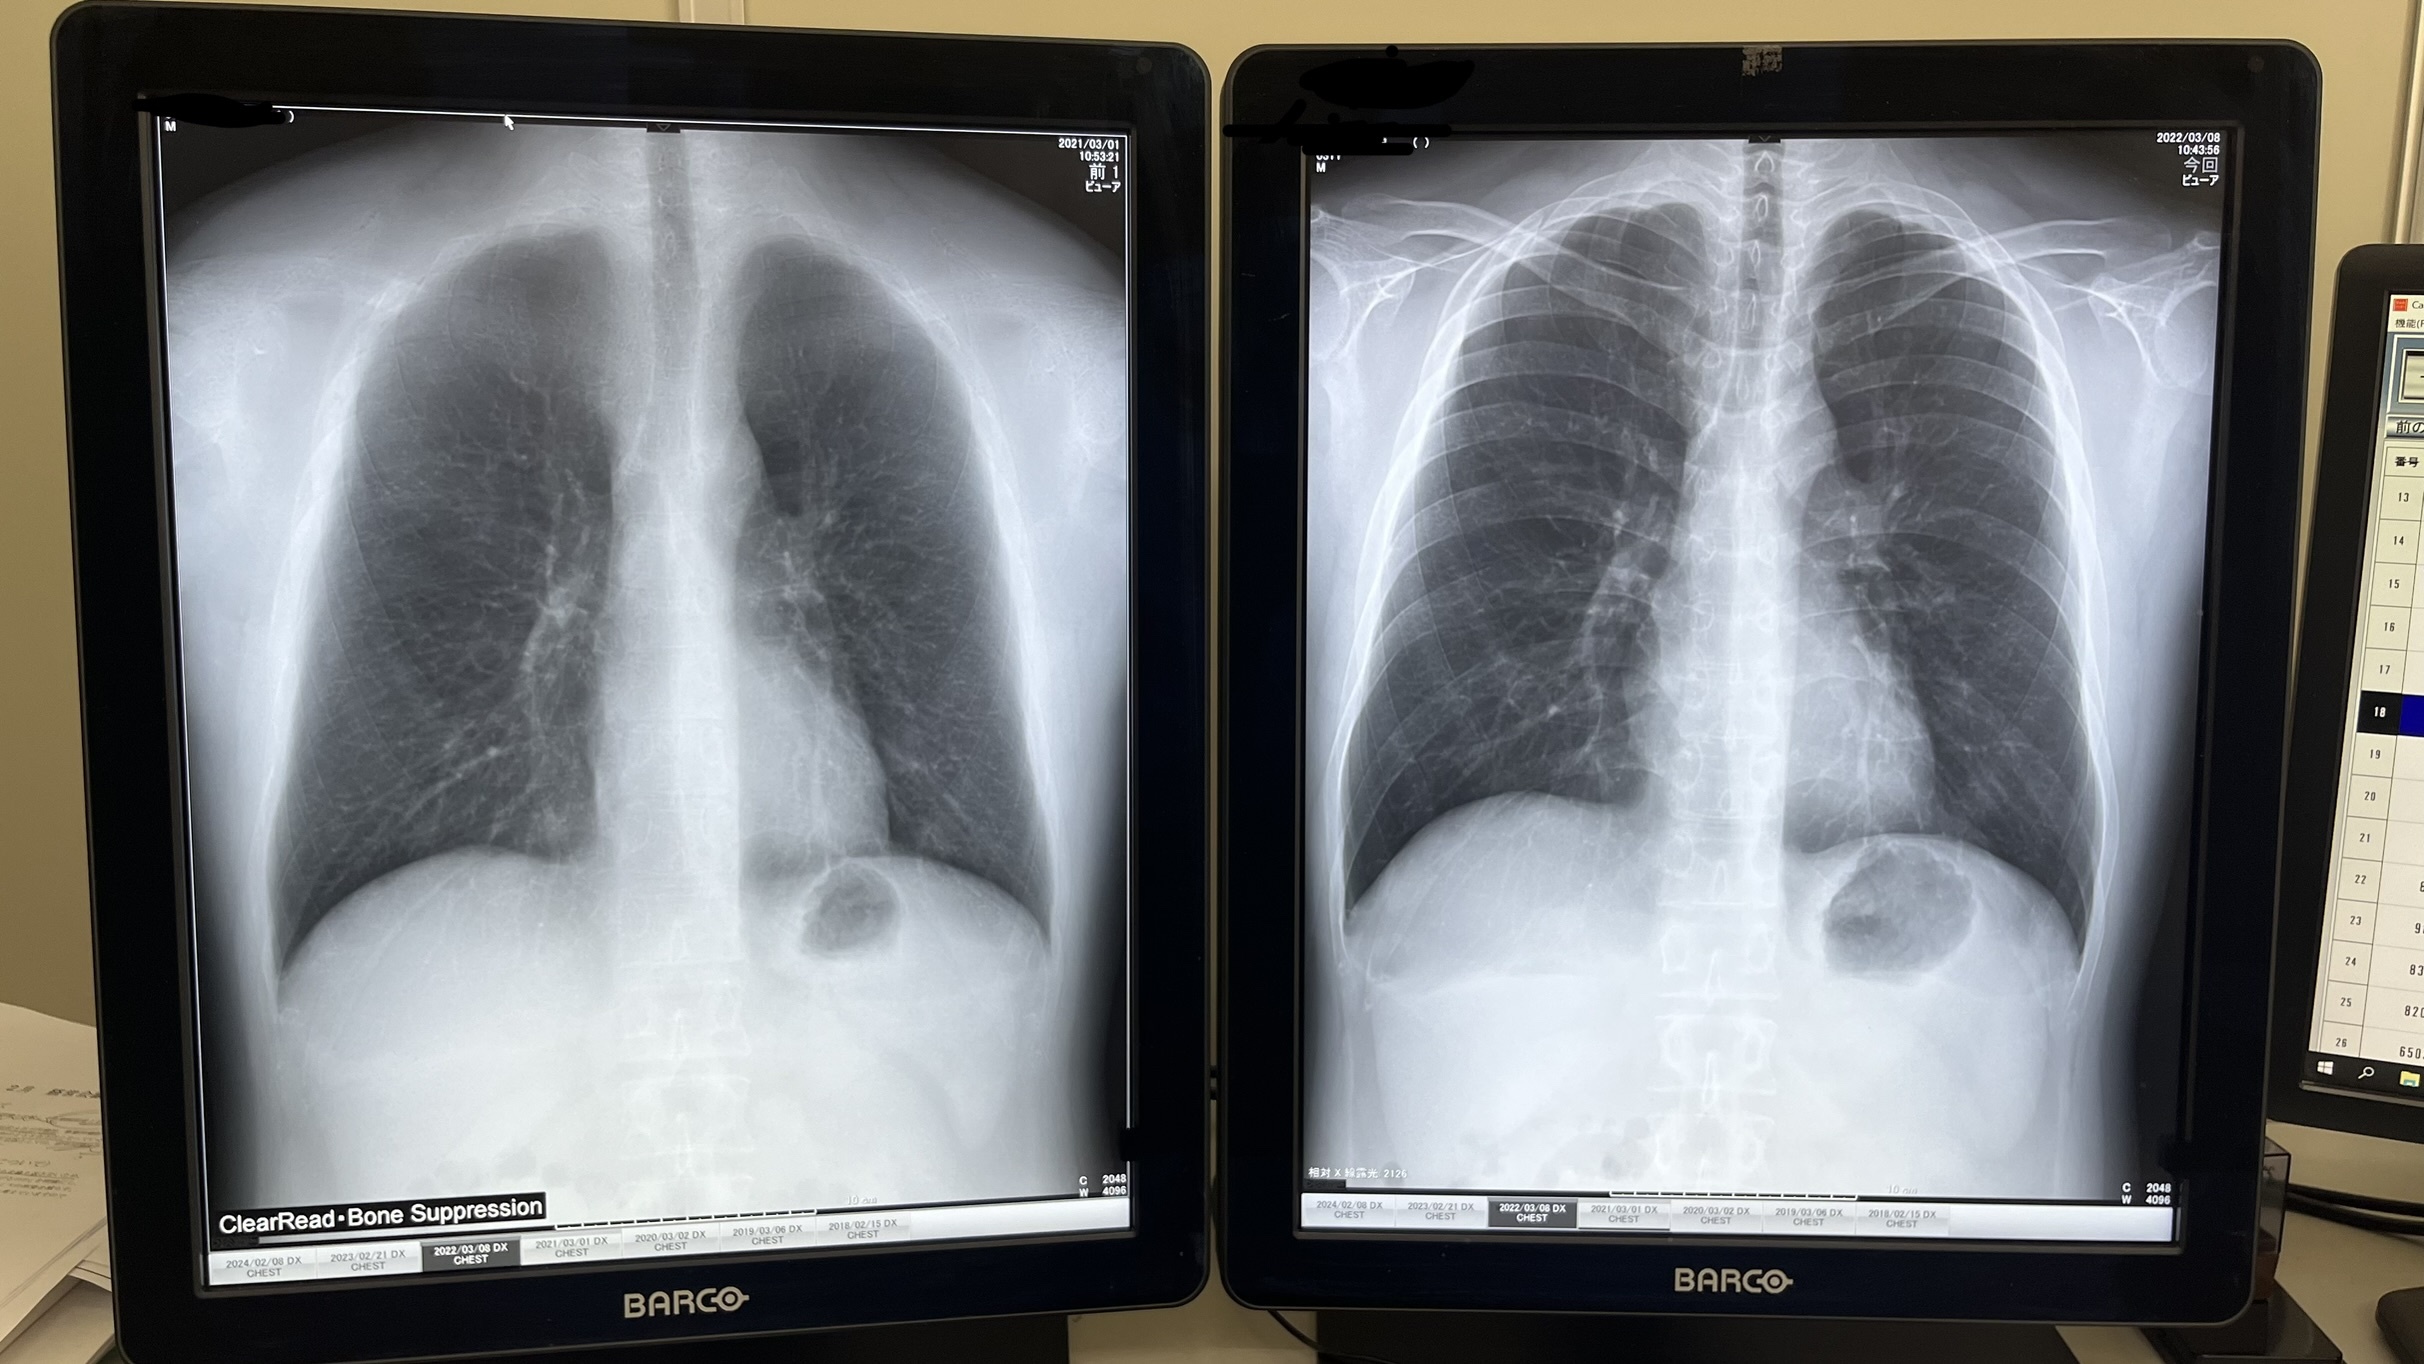

レントゲン室(X線検査を行います)

一般撮影装置

胸部レントゲンなどを撮影します。